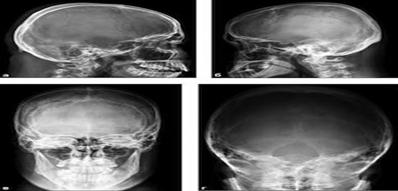

Невропатолог-дәрігердің тексеру қорытындысы – неврологиялық диагноз болып табылады. Айта кету керек, қосымша бағалы мәліметтер краниография, электроэнцефалография (ЭЭГ) және эхокардиография (ЭхоЭГ) сияқты зерттеулерді қолданған кезде алынуы мүмкін.

Краниография – көмегімен бас миының сүйегіндегі туа біткен кемістіктер, сондай-ақ бас сүйектің ерте таралуы мен өсу ерекшеліктері анықталады.